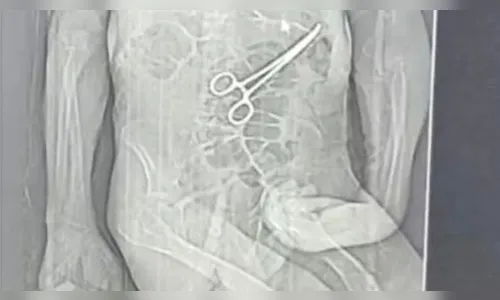

A família de Manoel Cardoso de Brito, de 68 anos, acusa o Hospital Municipal de João Pinheiro, no Noroeste de Minas, de falha médica após a morte do idoso, ocorrida na véspera do Natal. De acordo com os parentes, uma pinça cirúrgica teria sido esquecida no corpo do paciente após a primeira cirurgia, situação que só teria sido descoberta depois do óbito. (Foto abaixo)

Segundo o advogado da família, Iuri Evangelista Furtado, as providências legais foram adotadas após a divulgação, por uma rádio local, de uma tomografia que indicaria a presença do instrumento cirúrgico no corpo do paciente. Ele afirmou que acompanha a investigação conduzida pela Polícia Civil e que irá solicitar todos os prontuários, laudos, exames e registros clínicos e administrativos do hospital.